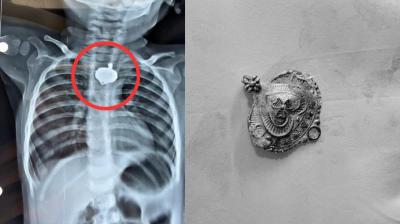

बड़वानी में 9 माह के बच्चे की आहार नली में फंसा मंगलसूत्र, डेढ़ महीने बाद एक्स-रे से खुलासा

24 Nov, 2025 08:30 AM IST | TRIPURITIMES.COM

बड़वानी: रविवार को जिला अस्पताल में एक बेहद संवेदनशील और हैरान करने वाला मामला सामने आया. जब 9 माह के एक बच्चे के गले में मंगलसूत्र फंसा हुआ देखा गया. घटना...